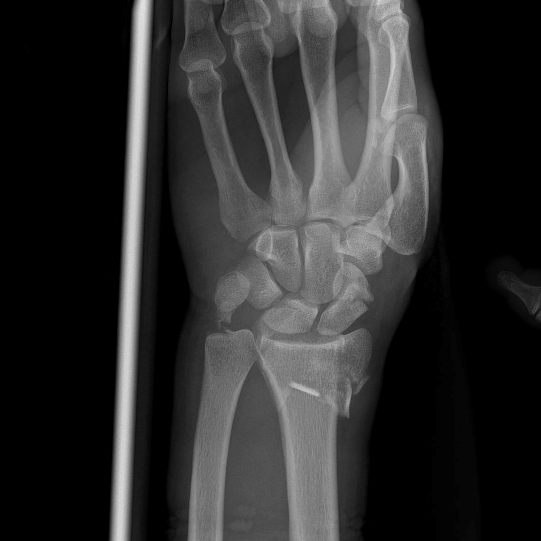

Dopo un normale e rapido stop durante la gara, tornavamo tra le ammiraglie quando c’è stata una frenata improvvisa, un corridore che mi ha precedeva non ha visto ed è caduto proprio davanti a me a 60 kmh… La conseguenza per me è una tripla frattura del radio, una frattura scomposta dello scafoide e una frattura dell’ulna… Inutile dire quanto sono demoralizzato, ancora una volta userò tutte le mie energie per tornare più forte di prima…